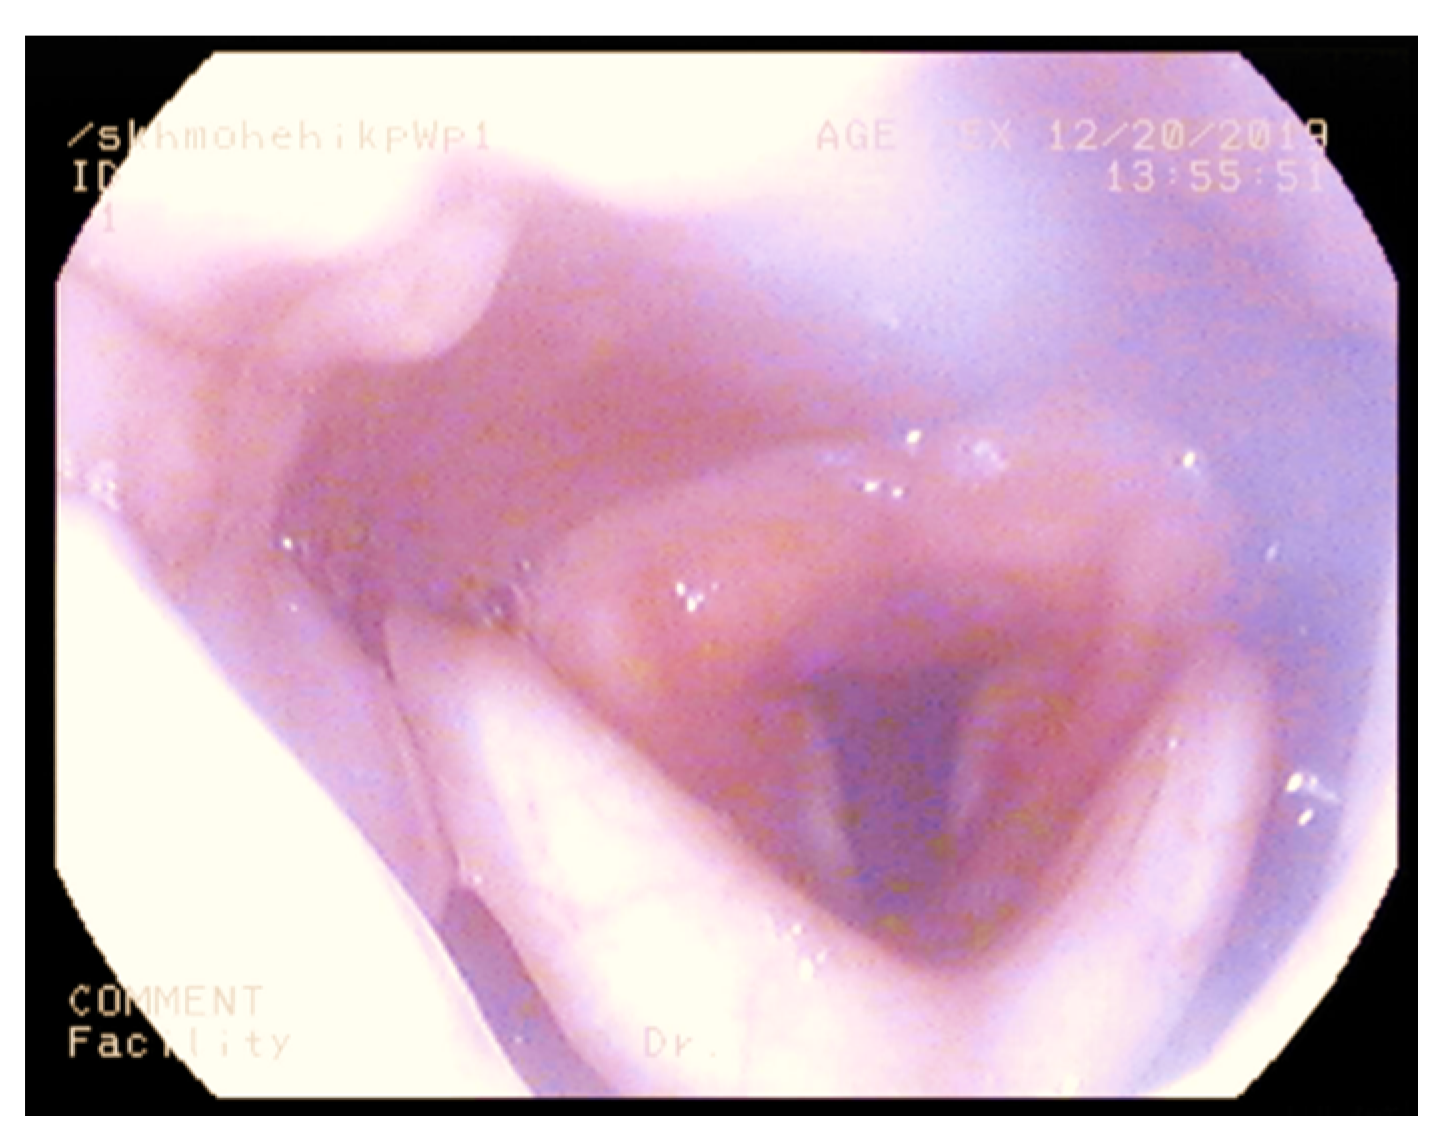

3.1. Nasendoscopy

- Epiglottis bulkiness on nasendoscopy / scan.

- Normal= 0 score (filling less than less than 1/3 of oropharynx)

- Mild bulkiness = 1 (filling 1/3–1/2 of oropharynx)

- Moderate bulkiness = 2 (filling 1/2 to complete oropharynx)

- Severe bulkiness = 3 (filling the entire oropharynx) *

- Supraglottis bulkiness on nasendoscopy/scan.

- Normal= 0 score (filling less than less than 1/3 of supraglottis)

- Mild bulkiness = 1 (filling 1/3–1/2 of supraglottis)

- Moderate bulkiness = 2 (filling 1/2 to complete supraglottis)

- Severe bulkiness = 3 (filling the entire supraglottis) *

- Glottis bulkiness on nasendoscopy.

- Normal = 0 score (filling less than less than 1/3 of glottis)

- Mild bulkiness = 1 (filling 1/3–1/2 of glottis)

- Moderate bulkiness = 2 (filling 1/2 to complete glottis)

- Severe bulkiness = 3 (filling the entire glottis) *